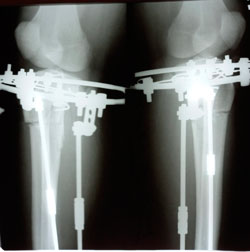

на фиксации

image-05-04-21-09-40-3.jpg

image-05-04-21-09-40-2.jpg

image-05-04-21-09-40-1.jpg